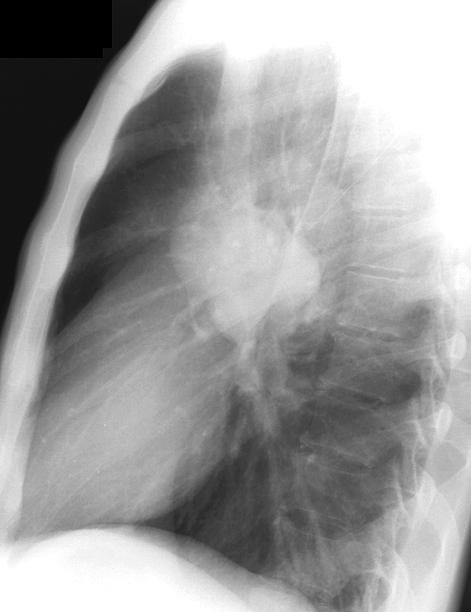

Gallery Mediastinum Lymphoma 1b

1b